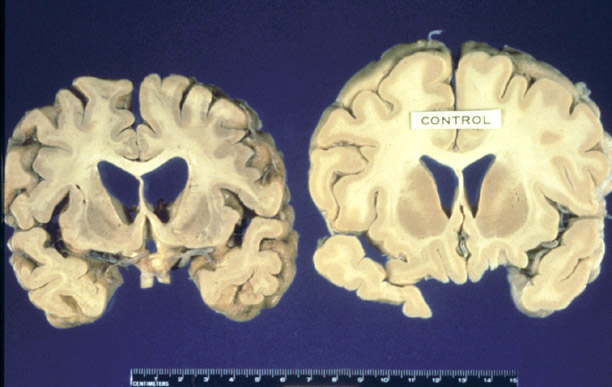

Creutzfeldt-Jakob disease (CJD): High Profile Case Gallery Creutzfeldt-Jakob disease (CJD): High Profile Case By Nicole Angemi|2022-01-06T10:52:15-05:00March 15th, 2021|The Gross Room, DISSECTIONS, MEDICAL| Read More 65